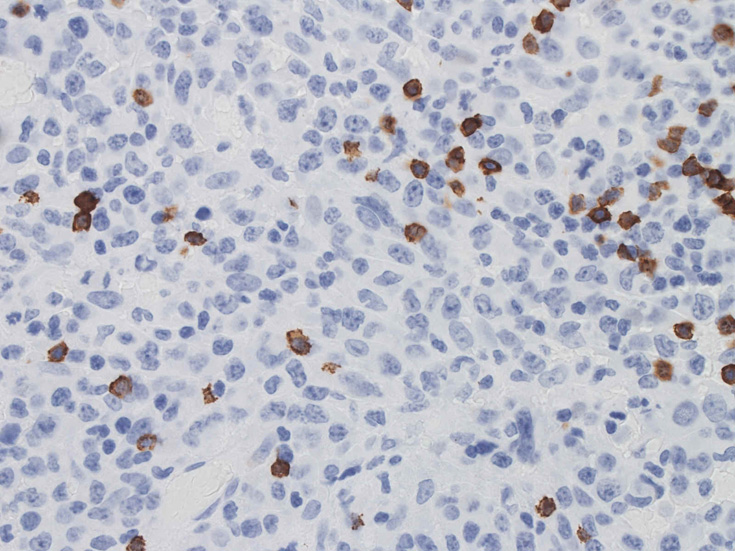

CD30はほぼ全ての腫瘍細胞に陽性となる。膜とゴルジ装置が染まり, 図のように細胞質内に斑点状の染まりが認められます。この症例では多くの腫瘍細胞がCD5陽性となり、CD30と同じ染色パターンを呈しました。